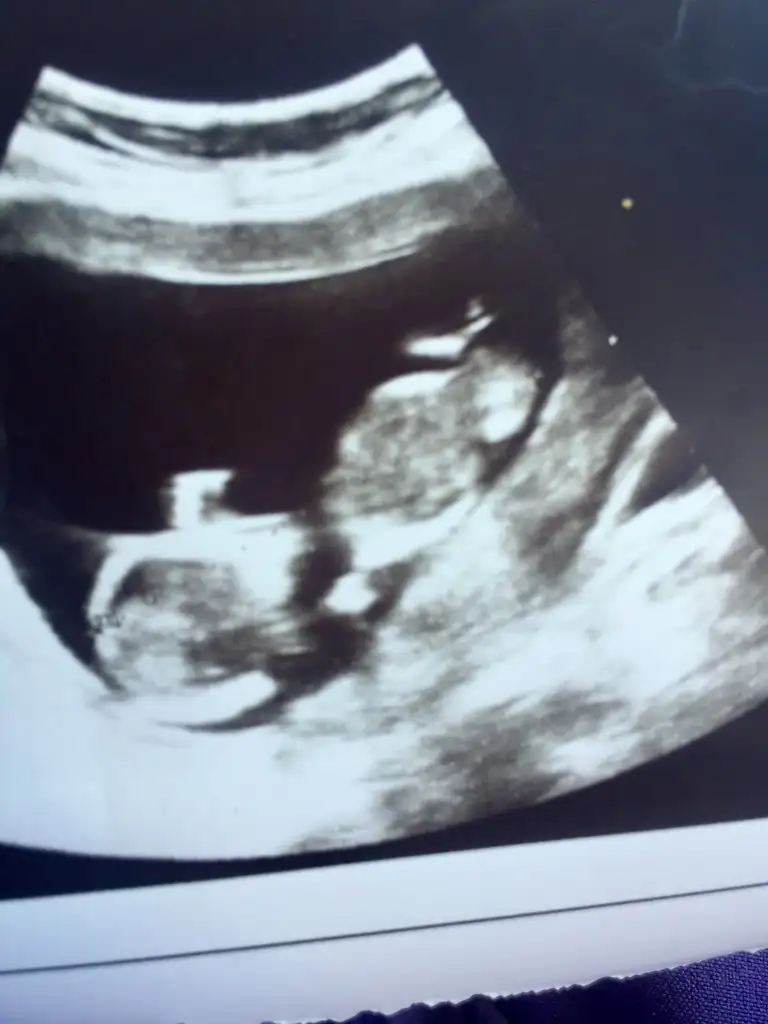

Eklentiler

• AF424906-4BC7-4D35-9DFE-EDDBC356532C.webp

AF424906-4BC7-4D35-9DFE-EDDBC356532C.webp

44,2 KB · Görüntüleme: 74